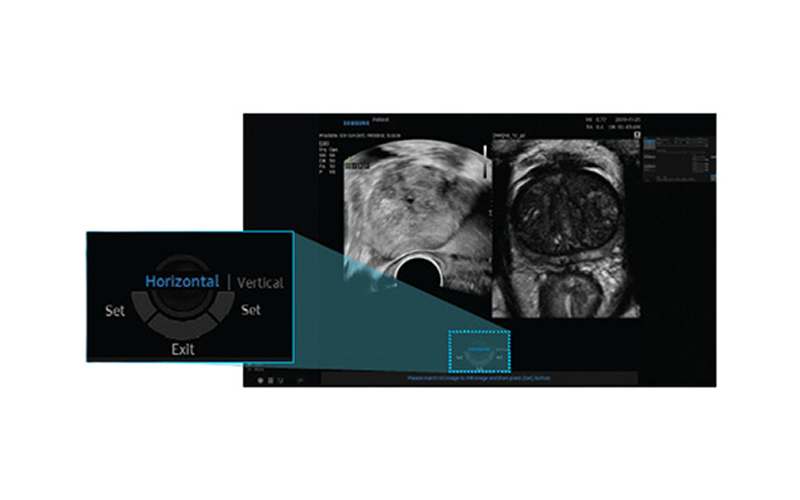

최첨단 AI와 3D 융합 영상으로 진단 정확도를 혁신적으로 높인 골드만만의 특별한 조직검사입니다.

기존 검사는 병변 유무와 관계없이 12군데를 무작위로 채취해 정확도가 낮고 재검 가능성이 높았습니다. 하지만 MR 퓨전 조직검사는 병변을 직접 겨냥해 조직을 채취하므로 진단율이 크게 향상되었습니다.